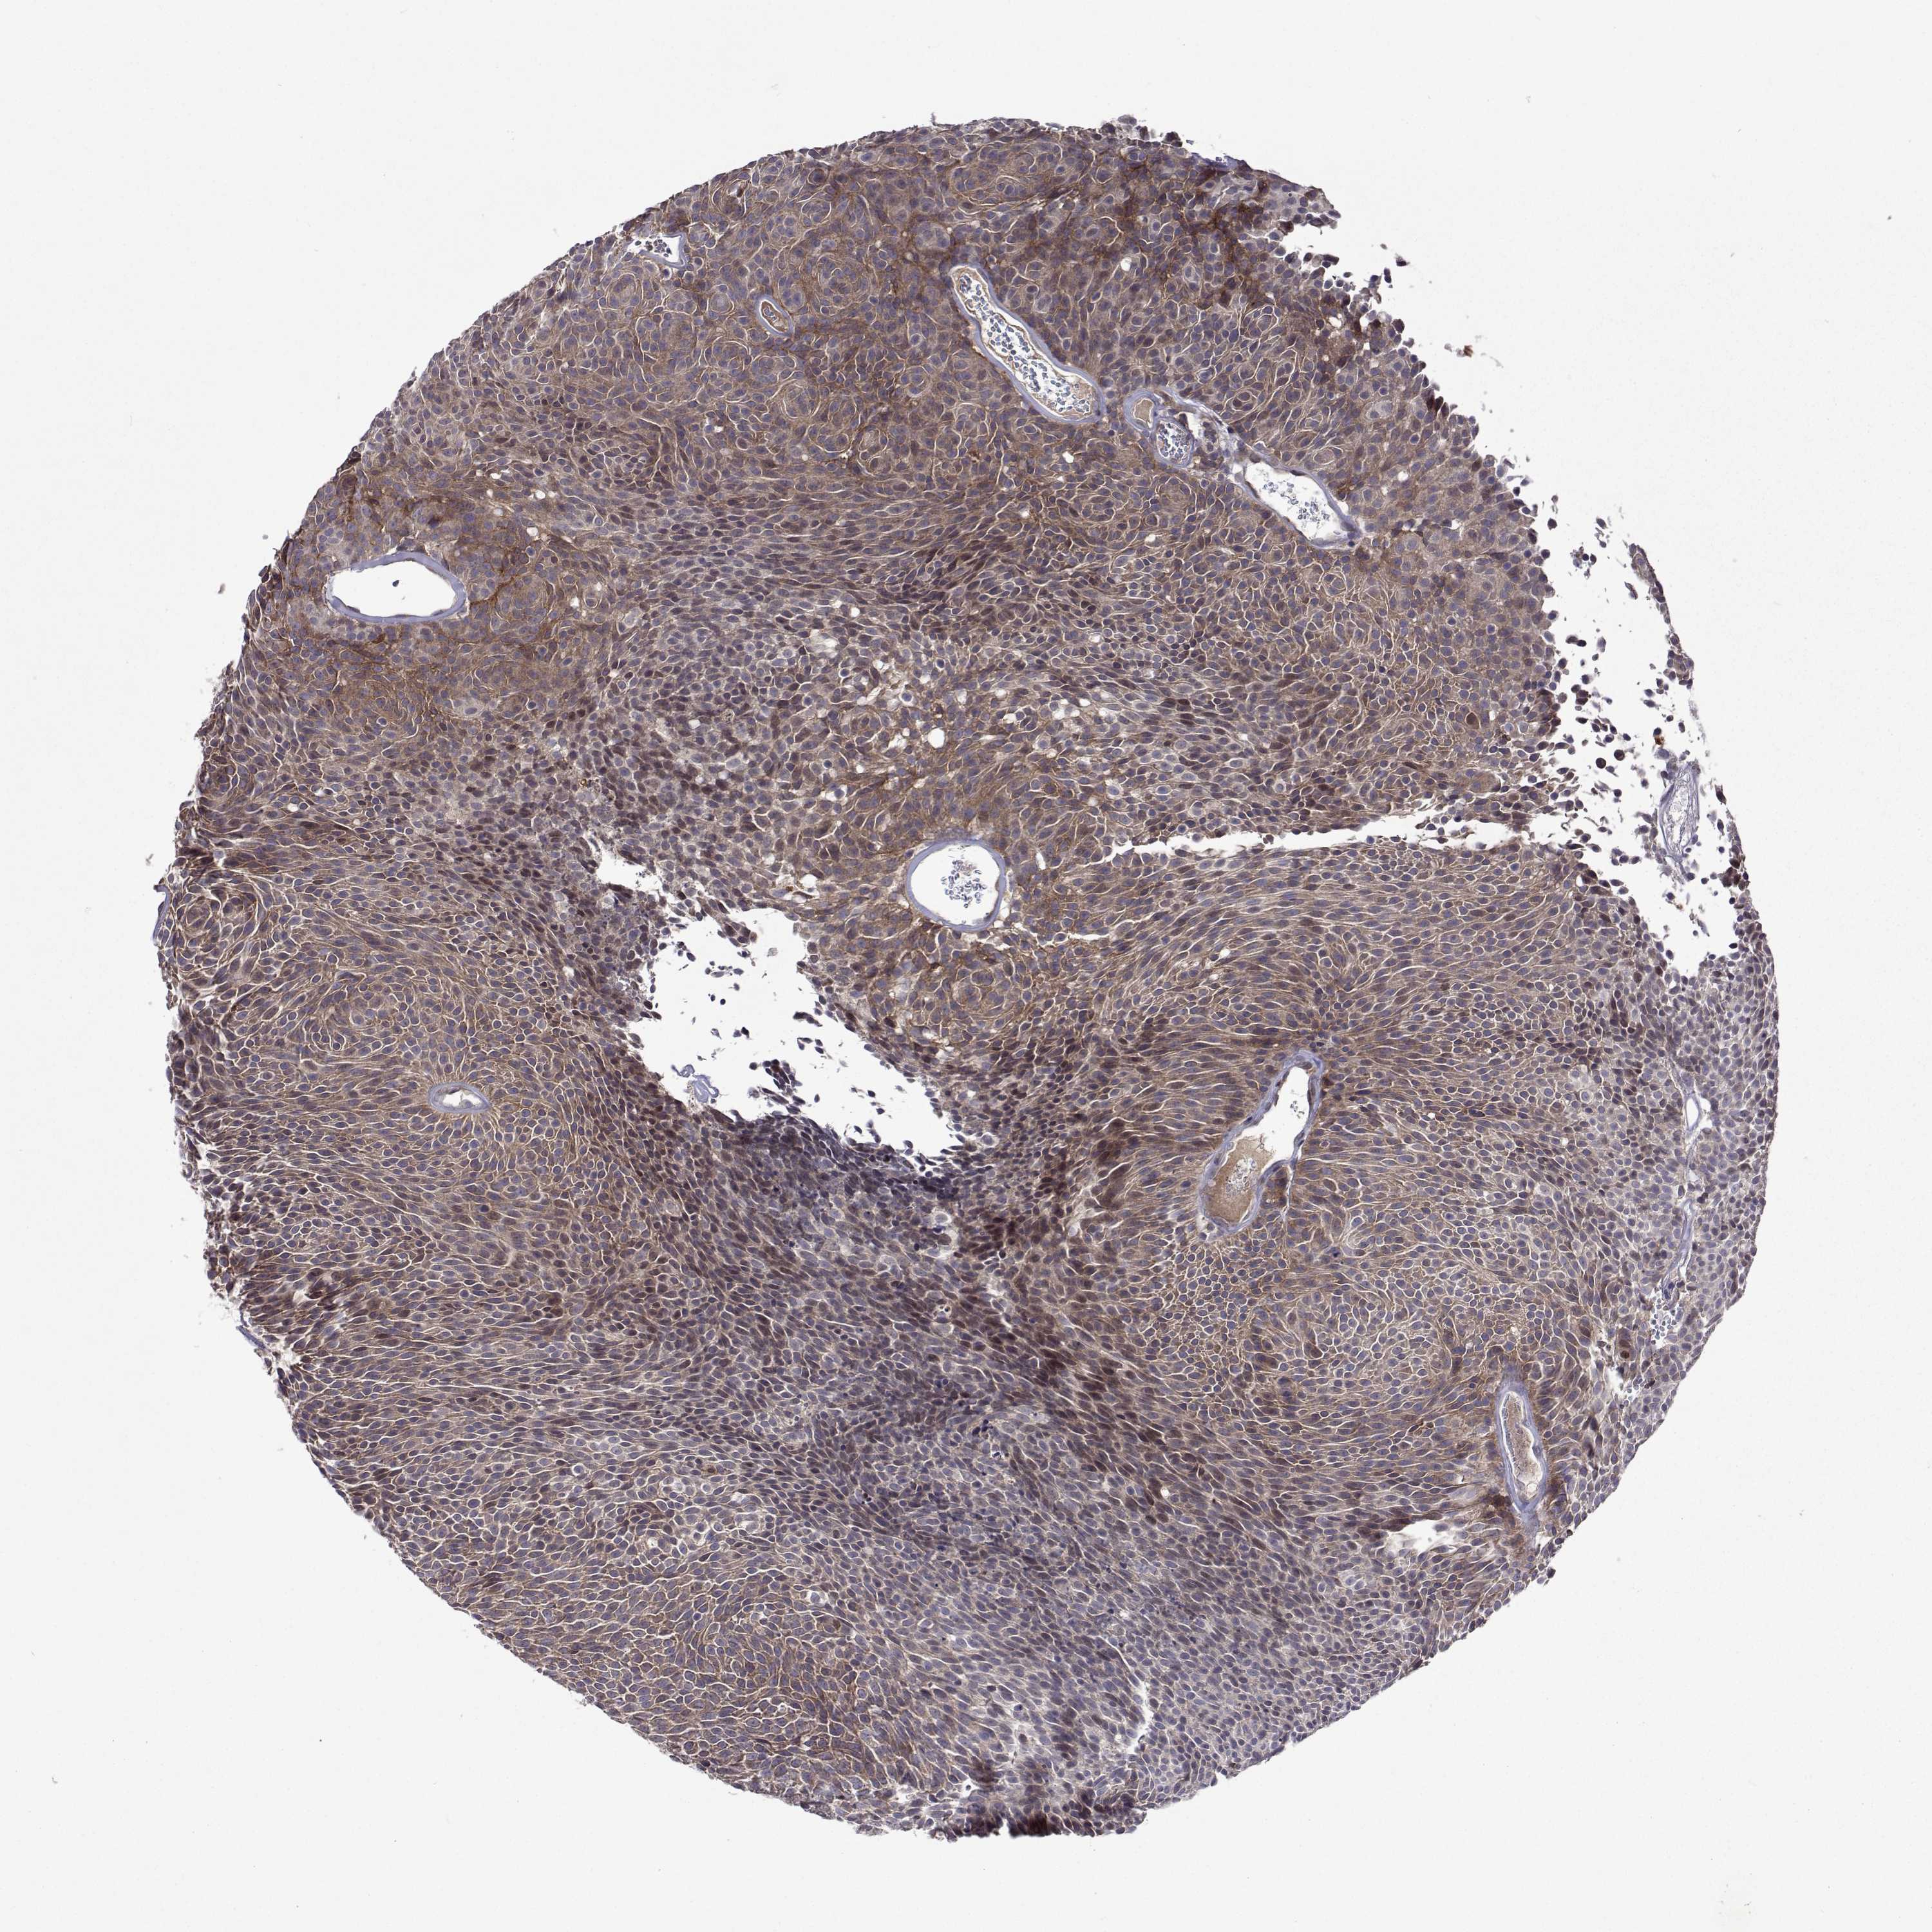

UROTHELIAL CANCER - Protein expressioni

A mouse-over function shows sample information and annotation data. Click on an image to view it in a full screen mode. Samples can be filtered based on level of antibody staining by selecting one or several of the following categories: high, medium, low and not detected. The assay and annotation is described here.

Note that samples used for immunohistochemistry by the Human Protein Atlas do not correspond to samples in the TCGA dataset.

Antibody stainingi

Antibody staining in the annotated cell types in the current human tissue is reported as not detected, low, medium, or high, based on conventional immunohistochemistry profiling in selected tissues. This score is based on the combination of the staining intensity and fraction of stained cells.

Each image is clickable and will lead to virtual microscopy that enables deeper exploration of all samples and also displays staining intensity scores, fraction scores and subcellular localization as well as patient and tissue information for each sample.

Antibody HPA051181

Antibody HPA061454

Antibody CAB069406

Urothelial carcinoma, High grade

Urothelial carcinoma, Low grade

Urothelial carcinoma, NOS